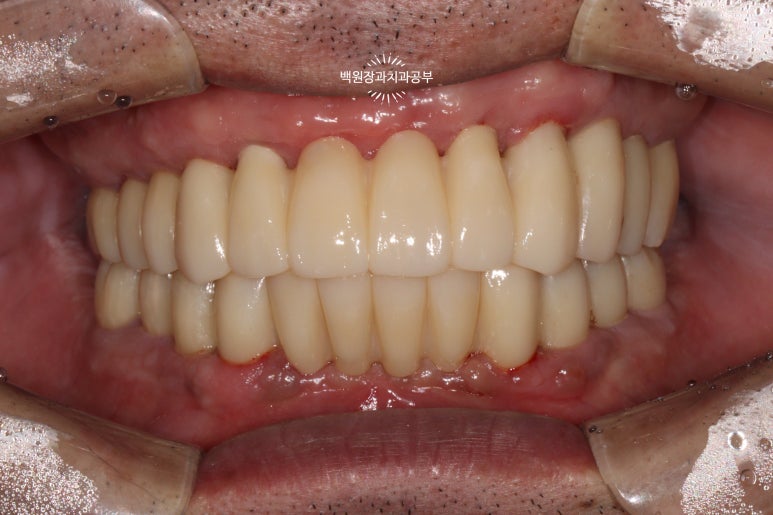

최종 보철물.. 드디어 제작이 되었습니다.

전체 임플란트를 완성하는데 전체 치료기간은 약 8개월 정도 걸렸습니다. 상당히 빨리 졸업하신 편이에요!

정면에서 보시면 임시 치아와 다르게 훨씬 깊이감 있는 색상으로 제작되어 자연스럽고, 완성도 있는 형태를 확인하실 수 있습니다.

그리고 치과용 파노라마로 확인해보시면, 정확한 위치에 정확한 보철물이 제작되어 상당히 조화로운 결과를 확인하실 수 있으실거에요! 치과의사로 살면서 가장 기쁘고 감동적인 순간 중 하나입니다.

정말 너무너무 보람찹니다 :) ㅎㅎ 환자분께서도 굉장히 만족해하셨어요!

금호동 전체 임플란트 전문 치과 대표 원장인 저와 보철과 원장님이 함께 최선을 다해 작업하였습니다.!!